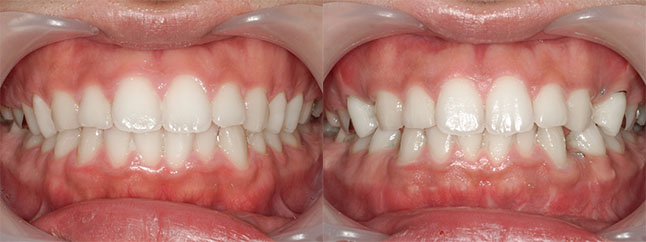

大阪府 22歳 女性

執刀医 辻和志

【治療内容】上のアゴと下のアゴの両方にこんもり感があったため、上下のアゴの骨をきって後ろに下げました。

【費用】上下セットバック 2,307,800円(税込)

【リスク】全身麻酔で行うため全身の健康状態が悪い方は行うことができません。また、手術当日は安静にしていただく必要があります。